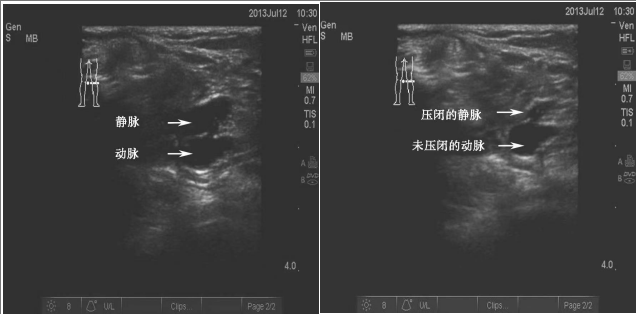

③远端加压信号增强法

打开超声的彩色多普勒血流显像时,可以看见红色和蓝色血流,颜色的亮度代表了血流的速度,血流速度越快,颜色越亮。利用这个原理,可以在目标血管远端挤压肌肉组织,这会使静脉在短时间内回心血量增加,血流速度加快,血流的颜色会短暂变亮,而伴行动脉无此变化,从而确定这变亮的血管为静脉。